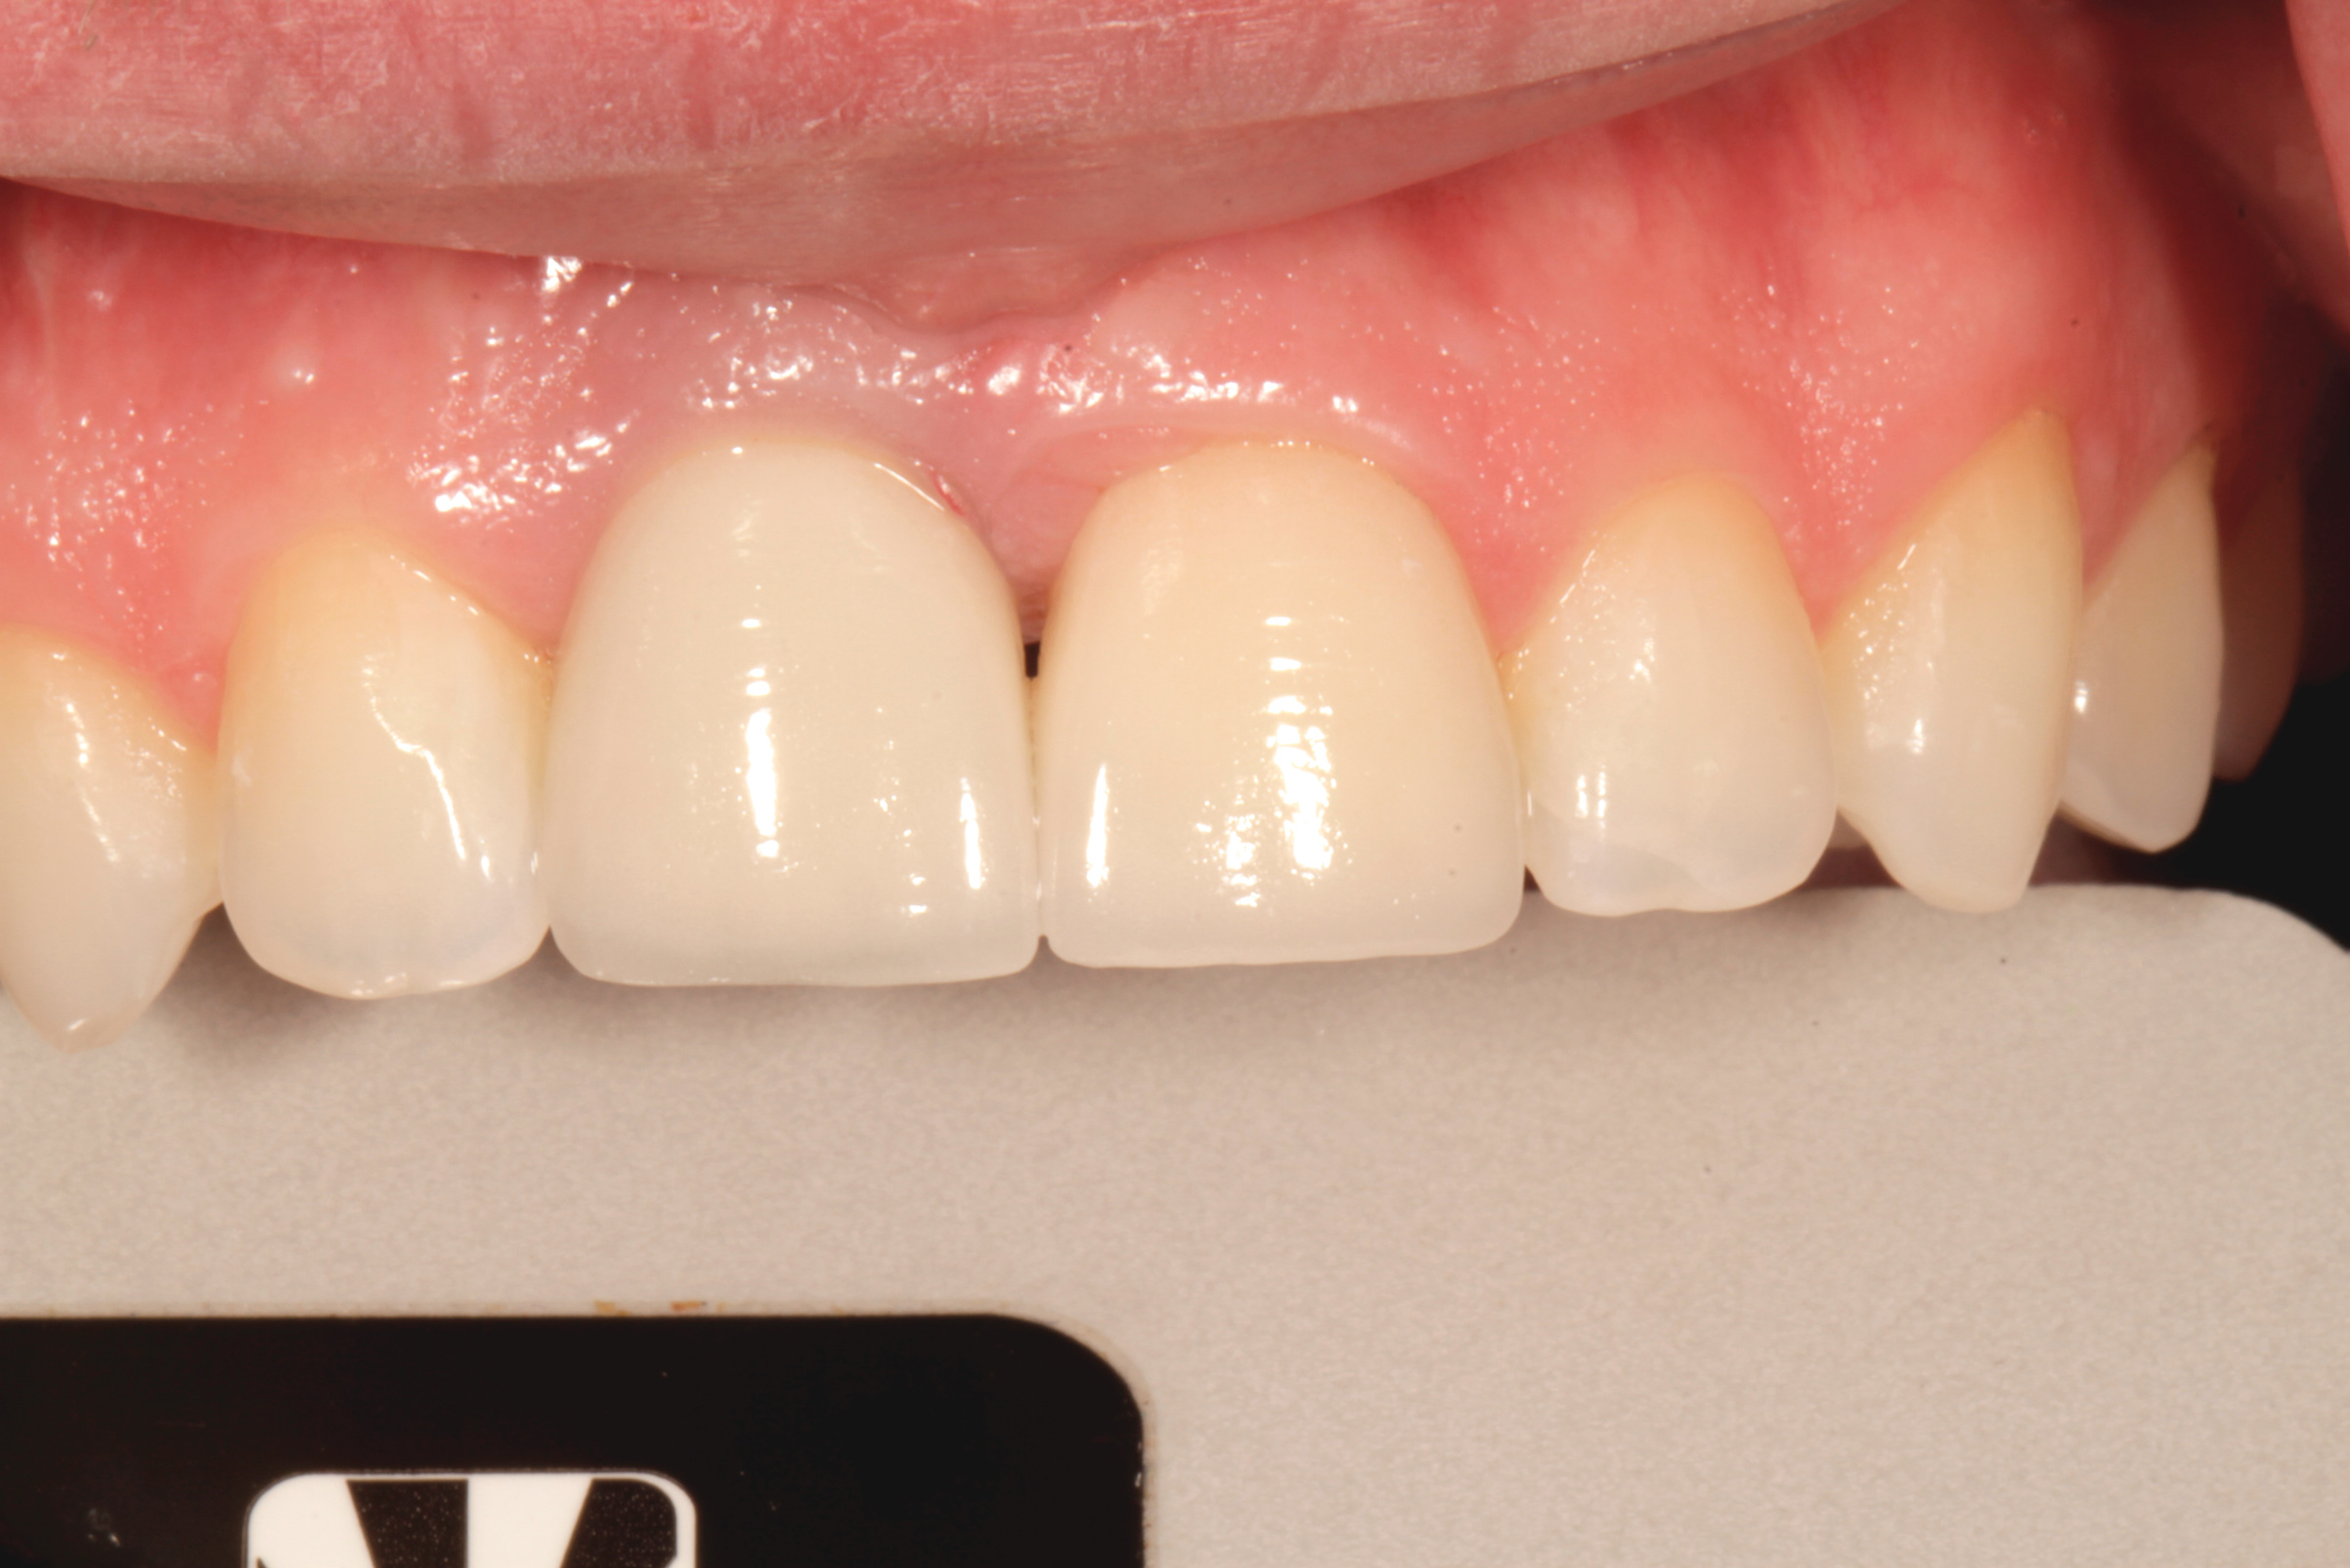

Fig 8. Age 19. Facial view of the ridge.

Figure 8

Fig 5. Age 15. Facial view of the developing ridge after removal of coronal segment of tooth No. 8.

Figure 5

After that the patient was seen in the endodontic office periodically to monitor the retained roots and associated alveolar ridge. The root of No. 8 was retained for 8 years after fracturing, and the root of No. 9 was retained for 9 years. During that time there were no clinical signs or symptoms, nor were there radiographic signs of periradicular breakdown. A final endodontic check at age 19 found the coronal surface of the root of No. 9 had been exposed. The vertical level and horizontal width of the alveolar ridge appeared very similar relative to the adjacent teeth as it had been at ages 10 and 15 (Figure 8 and Figure 9). No evidence of periradicular breakdown appeared radiographically (Figure 10). The patient's growth was deemed nearly completed and he was referred to an oral surgeon for evaluation and placement of implants.

From age 8 to age 19, midfacial skeletal growth occurs. Without a tooth, the alveolar ridge does not fully develop vertically and the ridge loses about one-third of its labial width after the tooth is lost.16,17 In case 1, clinical photographs and radiographs were routinely obtained. When compared, photographs taken at different ages appear very similar in both the facial (Figure 5 and Figure 8) and occlusal views. The levels of the tissue in the edentulous area relative to the incisal edges of the lower anteriors were quite comparable, as were the levels of the papillae on either side of the site. The width of the alveolar ridge in the extraction sites looked much the same from occlusal views (Figure 4, Figure 6, and Figure 9).